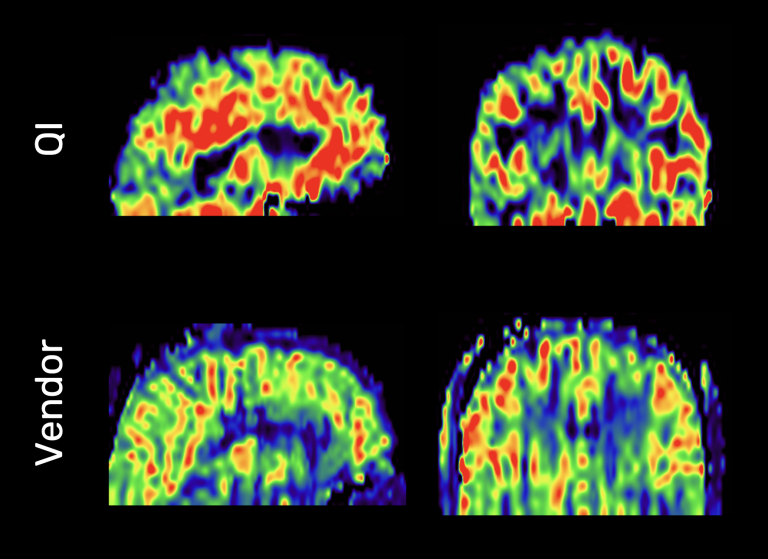

Patented deblurring technology substantially increases the accuracy and contrast of CBF maps when using 3D readouts such as GRASE.

Comparison of deblurred (top) and uncorrected CBF maps from a 3D GRASE sequence at 3T.